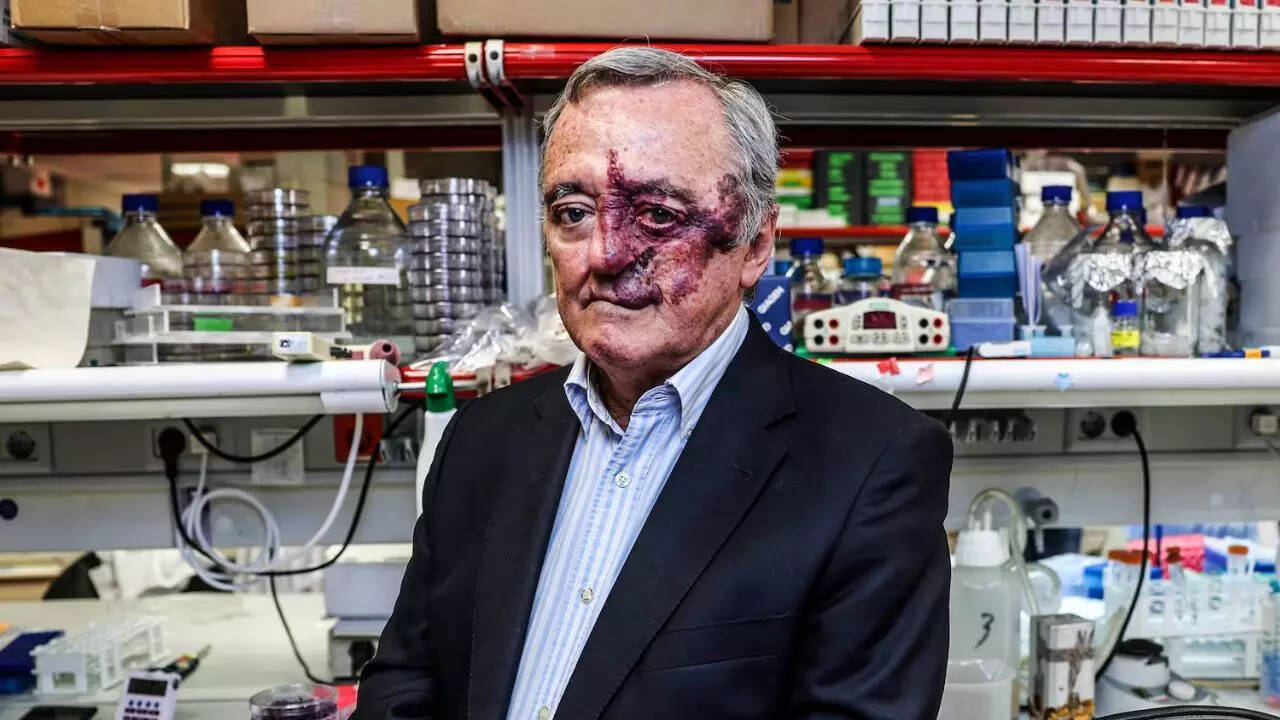

Gordon Ramsay undergoes skin cancer surgery

2025-08-31